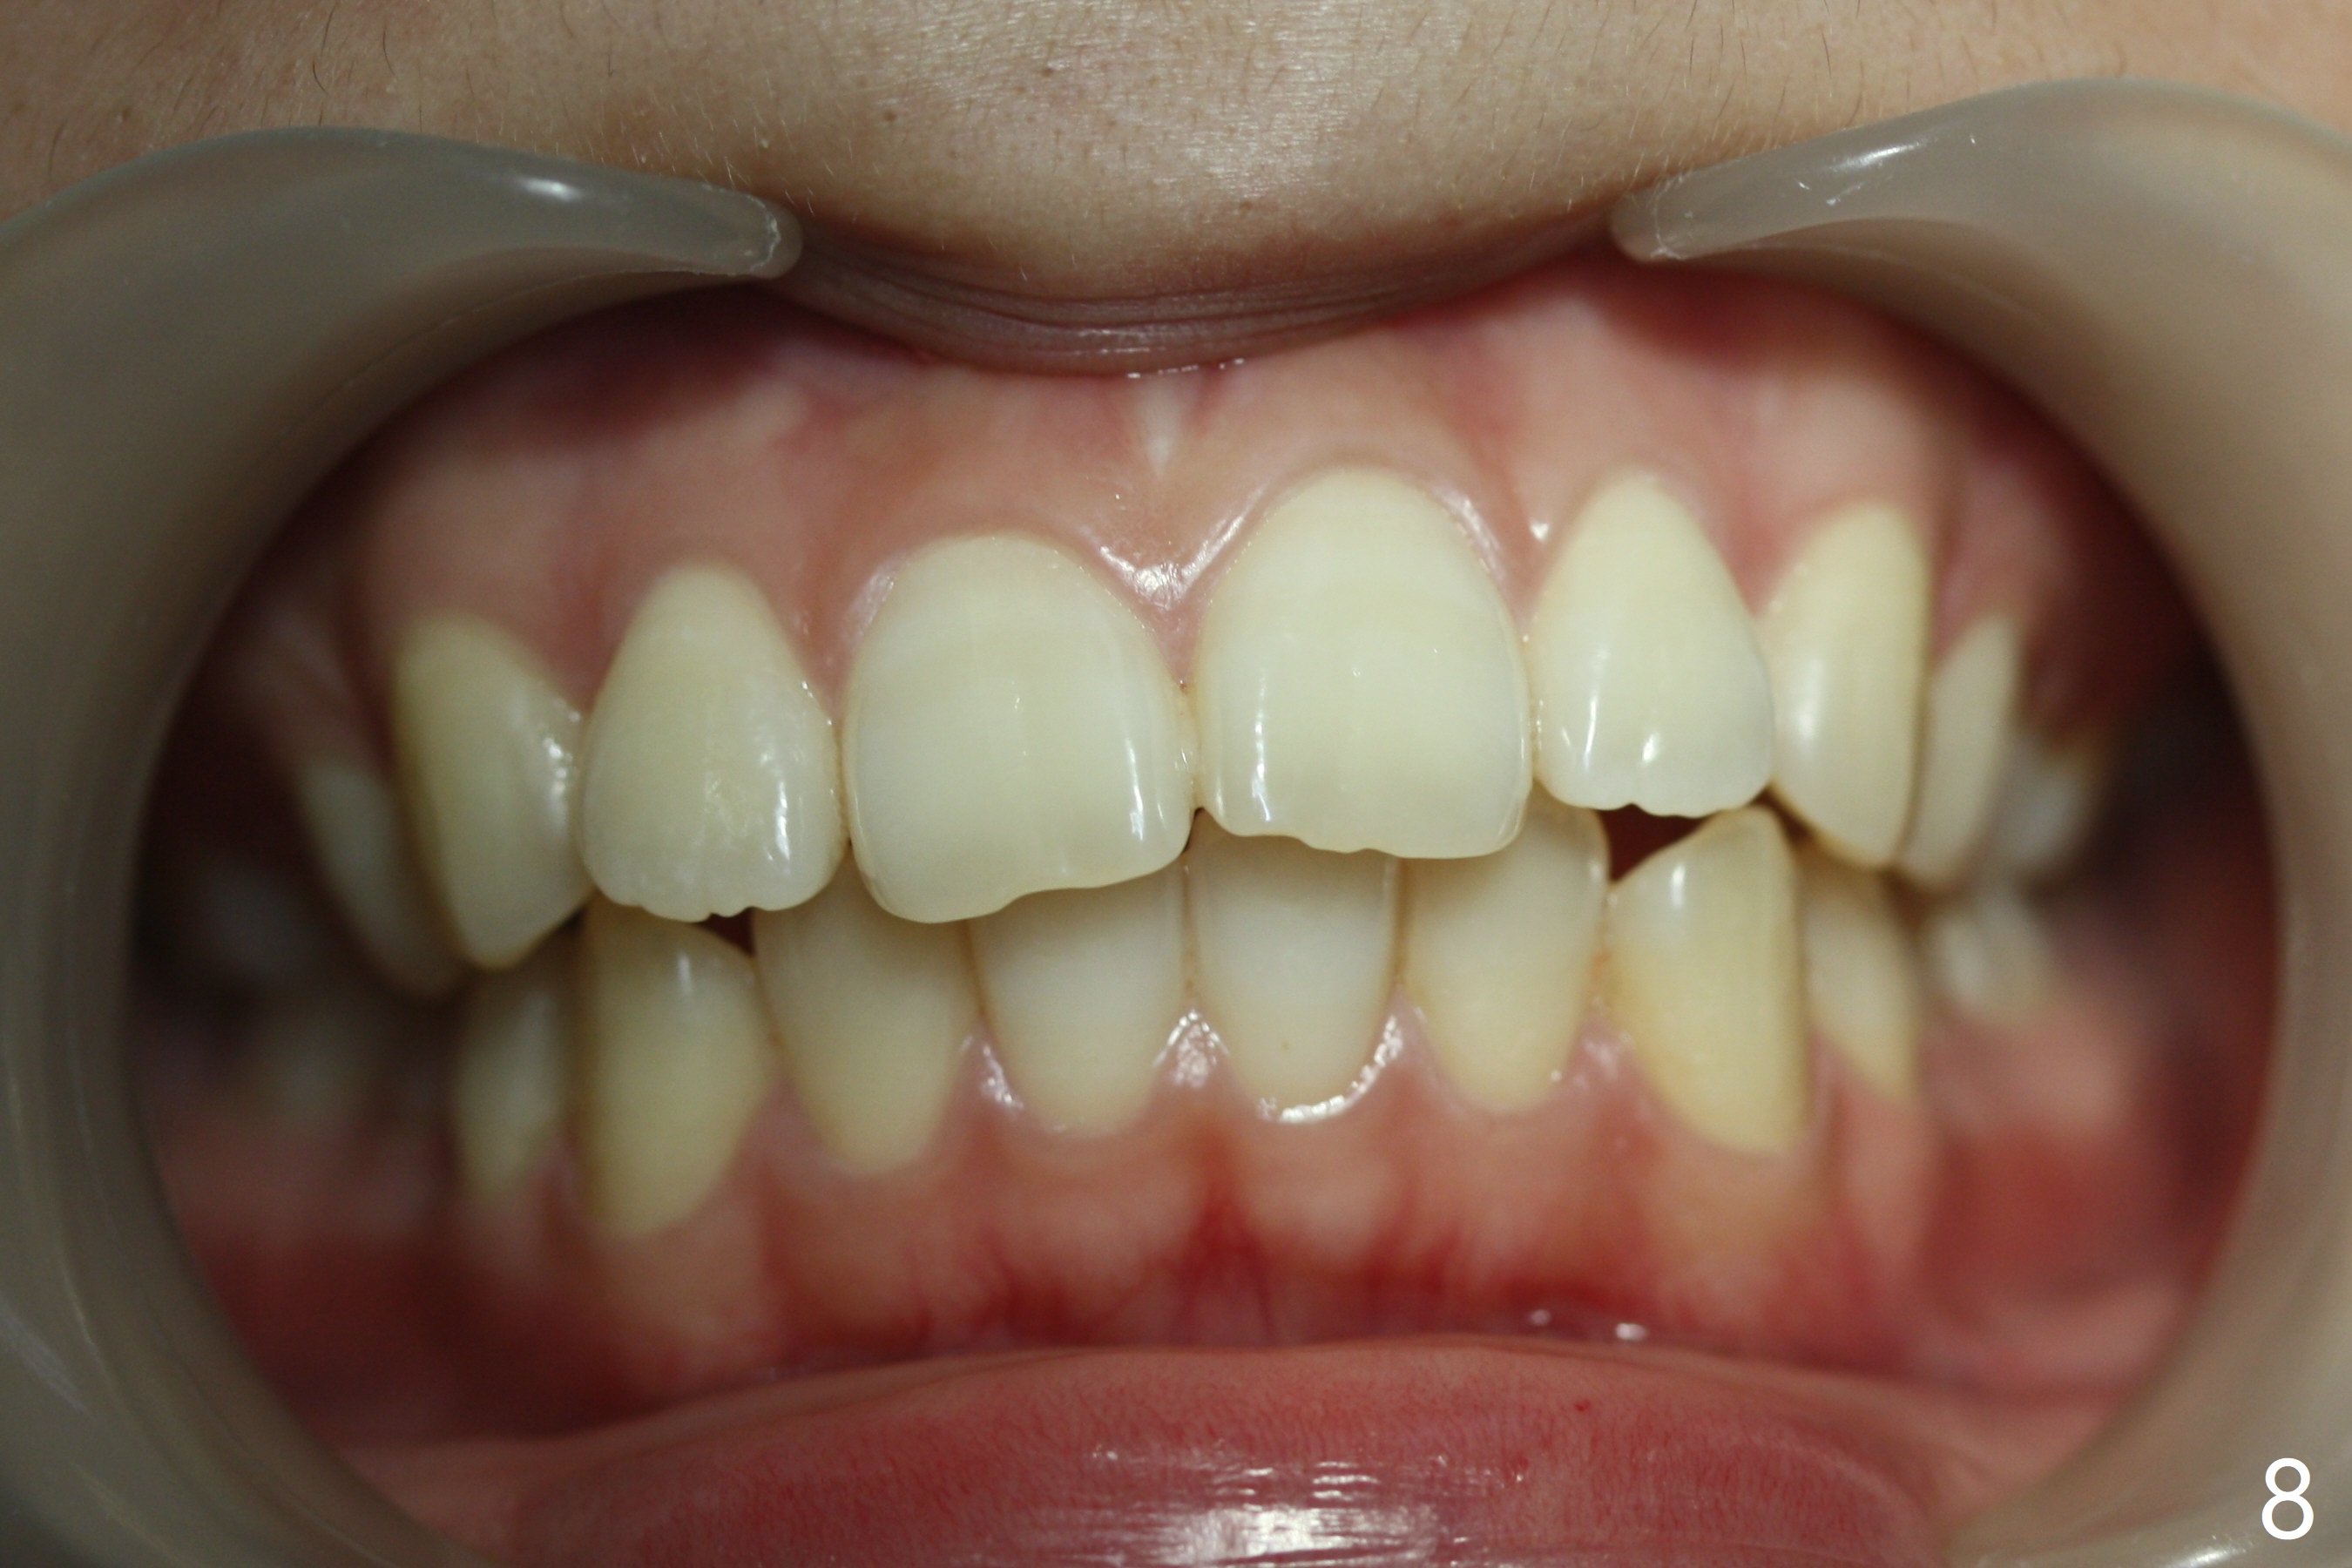

A 15-year-old woman has protrusive lips and retrusive chin (Fig.1-6). Canines and molars have Class I occlusion (Fig.7-9). With 4 bi extraction and 5-7 anchorage (Fig.10-12), 3s will be distalized after 16x16 wires, followed by posted wire retraction of 4 incisors.